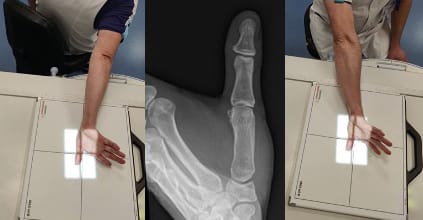

In 1936 the French radiologist Robert [8] Vigouroux F, Rabarin F, Jeudy J, Bigorre N, Saint Cast Y, Pechmajou L, Raimbeau G. Peritrapezial osteoarthritis: Inter – and intraobserver reliability of the Allieu classification. Hand Surg Rehab 36 (2017) 363-367 (Figure 6) described an anteroposterior view of the TMC performed in maximum anteroposterior pronation that it is useful to be familiar with. This view is very popular in the USA. It is taken with the patient’s back facing, avoiding irradiating the lower limbs.